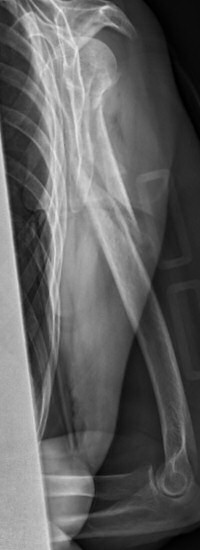

Exempel på humerusfraktur som behandlats icke-kirurgiskt, röntgenbilder efter 19, 40 resp. 71 dagar